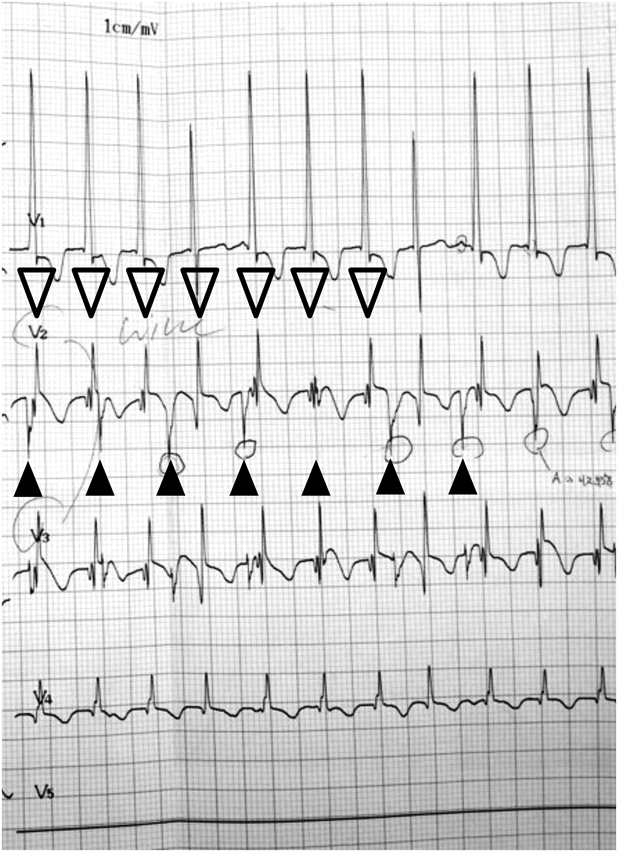

心拍数だけでなく心房心室収縮のタイミングも重要である.心房収縮は心拍出量に大きく影響し,術後急性期にはA-V intervalを少し変えるだけでCVPや血圧が大きく変動することが多い.またATやJETなどの頻脈性不整脈もよく起こるが8),胸部誘導では診断が困難なことがある.そのような場合には心房リードを直接心電図計に接続すると,心房電位がはっきり描出され診断が容易になる9)Fig. 2は胸部誘導心電図ではっきりしなかったJETが心房リード心電図により,心房電位が明確になりJETと診断できた例である.

Fig. 2 Electrocardiogram in patient with junctional ectopic tachycardia

Lead V2 and V3 are connected to atrial wires. Atrial activity (▲) is clearly seen in V2 and V3, but that is not obvious in regular pericardial lead V1 and V4 (top and bottom). Notice ventricular activity (▽) is faster than atrial activity.